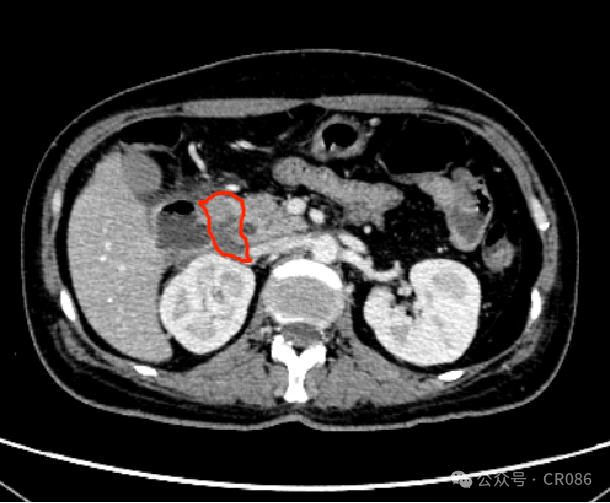

11月底,移植科医生发了一张CT影像报告给我,说:“洪飞,你还记的这个病人么?肿瘤已经快没了!”我对照了一下病情,不敢相信自己的眼睛。是的,袁姐之前半个腹腔的巨大肿瘤,在CT上已经只有一点点残留影子了。

2024年11月25日 2轮维奈克拉联合方案后

我问医生,怎么做到的?“很简单,我们用了维奈克拉联合的化疗方案”。他轻描淡写的得瑟着自己的成果。

“加了个维奈克拉,疗效就这么好么?”我问道。“是的,我们看了文献,这个类型,普遍是BCL-2高表达的,所以我们用BCL-2抑制剂维奈克拉来联合,理论上可以提高减瘤的效果,而实际上,这个疗效也足以说明问题。